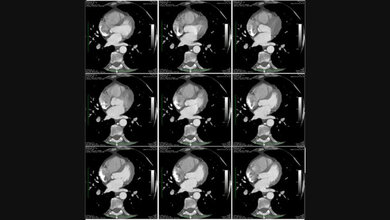

Auch technisch stellt die Anwendung einige Anforderungen an die Bildgebung, die über die im sonstigen Routinebetrieb hinausgehen, zum einen an die hohe zeitliche Auflösung – je kürzer, desto schärfer das Bild, zum anderen an eine hohe räumliche Auflösung, da zum Beispiel die Koronarien nur wenige Millimeter im Durchmesser aufweisen. Gerade beim Arbeiten mit älteren Geräten können sich hier jedoch große Probleme ergeben, weil bei diesen die zeitliche Auflösung unter Umständen nur 100 ms beträgt. Für hochauflösende Bilder der Systole, als Beispiel, ist jedoch eine Auflösung von 25 ms oder kleiner notwendig. Um zu belegen, in welcher Phase des Herzzyklus die einzelnen Bilder gemacht wurden, muss parallel zum Scan ein EKG aufgezeichnet und synchronisiert werden. Zudem ist die Cardio-CT, vor allem bei vielen Geräten älterer Generation, mit einer hohen Strahlenbelastung verbunden. Deswegen sind hierbei Maßnahmen, die Strahlendosis zu senken, stets dringend geboten. Bei vielen Fragestellungen ist es zum Beispiel nicht unbedingt notwendig, den gesamten Herzschlag aufzunehmen, sondern nur in jeweils einer Phase zu strahlen („prospektives Triggern“). Damit wird die Strahlenbelastung um circa das Fünf- bis Zehnfache gesenkt. Nachteil ist, dass bei Patienten/-innen mit Arrhythmien, die einen großen Teil der zu untersuchenden Klientel darstellen, diese Technik nicht anwendbar ist, da nicht genau vorhergesagt werden kann, wann eine Arrhythmie erfolgt, und es so zu Bewegungsunschärfen kommen kann.

Ist es erforderlich, alle Phasen darzustellen („retrospektives Gating“), zum Beispiel bei Patienten/-innen mit Arrhythmien oder zur Funktionsbestimmung, strahlt das CT über den gesamten Herzschlag in stark überlappenden Scans. Somit kann im Nachgang jede Phase einzeln rekonstruiert werden. Hierbei steigt aber auch die Strahlendosis enorm, weshalb genaues Abwägen daraus entstehender Risiken für den Patienten notwendig ist. Eine Möglichkeit, dabei die Dosis zu reduzieren, ist die Dosismodulation („ECG-Pulsing“). Bei dieser Technik wird festgelegt, in welcher Phase Bilder mit hoher Dosis aufgenommen werden, zum Beispiel Diastole (60 % des Zyklus). Danach wird die Dosis auf ein Minimum reduziert, um gerade noch Bilder zu erzeugen. Diese haben jedoch eine so geringe Auflösung, dass sie nur von computerbasierten Auswerteprogrammen ausgelesen werden können (zum Beispiel zur Volumenbestimmung). Sie sind jedoch nicht zur Befundung geeignet, da sie in der Qualität zu stark reduziert sind. Die Gerätehersteller bieten daher umfangreiche Nachbearbeitungssoftware für fast jede Fragestellung an. Für die Planung von Operationen zum Klappenersatz oder vergleichbaren Indikationen ist die Cardio-CT längst Voraussetzung.